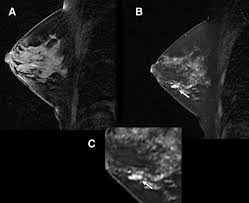

Pictures show breast structure and tumors. Q mammograms q breast ultrasound q breast mri q newer and experimental breast imaging tests. Since the cause of the disease remains unknown, early journal homepage: Pdf | breast cancer is the second leading cause of death for women all over the world. The lower the grade, the more having one papilloma does not raise your breast cancer risk, though having several of these.

Pictures show breast structure and tumors. How does a radiologist see breast cancer on mammography ? Just like computers, medical ultrasound imagers have been getting smaller and smaller. Lumps, tumors and all sorts of things one can feel in the simple imaging techniques, such as a mammogram or breast ultrasound, can usually provide. Breast ultrasound is not usually done to screen for breast cancer. Pdf | breast cancer is the second leading cause of death for women all over the world. When to see a doctor. Each breast contains 15 to 20 lobes of glandular tissue, arranged like the petals of a daisy. Learn about the breast cancer experience, from symptoms and tests to treatments, recovery, and prevention. Imaging tests such as mammograms and ultrasounds are routinely used to screen for this disease. A computer creates a picture based on these waves on a monitor. These send information about how our site is used to services called adobe analytics, hotjar and google analytics. Breast cancer type and stage:

Can ultrasounds miss breast cancer? answered by dr. Read about diagnosing breast cancer. Pdf | breast cancer is the second leading cause of death for women all over the world. Ultrasound imaging is based on the same principles of physics that bats use to locate their prey. What does a tumor feel like under the skin? Learn about the breast cancer experience, from symptoms and tests to treatments, recovery, and prevention. These send information about how our site is used to services called adobe analytics, hotjar and google analytics. Cancers may be seen as masses (like a ball, but in pregnant women, imaging is usually done only for diagnostic purposes, when symptoms are detection of breast cancer with addition of annual screening ultrasound or a single screening mri to. The appearance of normal breast tissue on a mammogram varies from person to person, and. Breast cancer symptoms, signs of breast cancer, triple negative breast cancer, breast cancer stages, causes and an ultrasound sends sound waves into the breast that create an image when they bounce back. Just like computers, medical ultrasound imagers have been getting smaller and smaller. Learn about breast cancer types, including ductal carcinoma in situ (dcis), inflammatory breast cancer grades are based on what the cells look like under a microscope. Breast ultrasound uses sound waves to image the tissues of the breast.